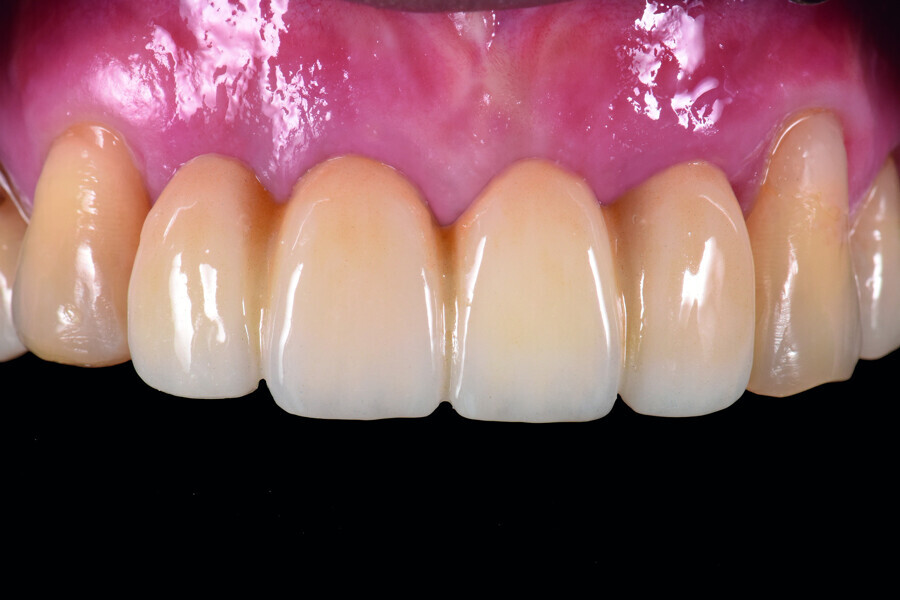

Fig. 11: The emergence profile three months post-op.